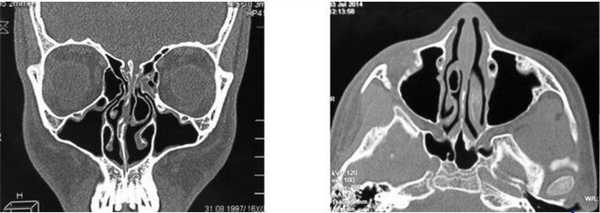

КТ околоносовых пазух ребенка с врожденной изолированной расщелиной неба во фронтальной и аксиальной проекциях - фото

Рентгенологические исследования в детском возрасте выполняют исключительно по жизненным показаниям, если результаты иных способов диагностики (эндоскопия, МРТ) требуют уточнения. Решение принимается коллегиально врачами нескольких специальностей. КТ носоглотки детям до 12 лет чаще проводят в отделениях лучевой диагностики при педиатрических клиниках. Не стоит отказываться от диагностики из-за ложных соображений о вреде для здоровья. В некоторых ситуациях (травма, подозрение на опухоль) последствия бездействия хуже выполненного КТ.